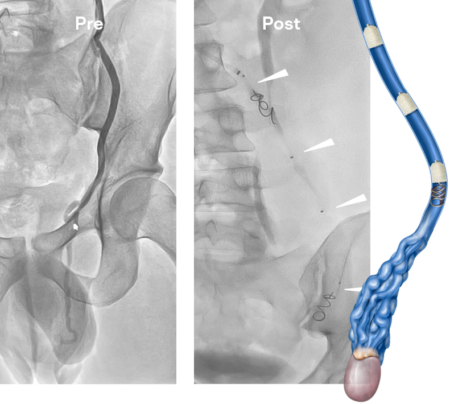

Testicular Vein Embolization

with IMPEDE & IMPEDE-FX

Images courtesy of Patrick Knüsel, MD Kantonsspital Graubünden, Chur, Switzerland

Ovarian Vein Embolization

Images courtesy of Andreas Hadjipolycapou, MD Apollonion Private Hospital, Strovolos, Cyprus